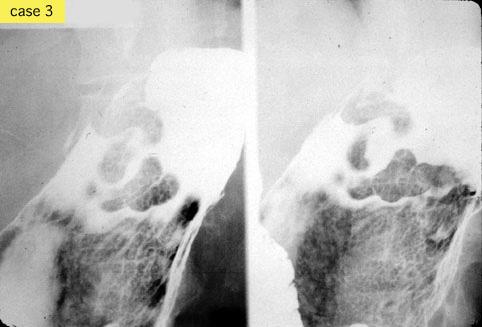

Several cases of typical gastric varices.

Tumor-like lesions/varices

Stomach/Gastroesophageal junction

X-ray

35 - 40